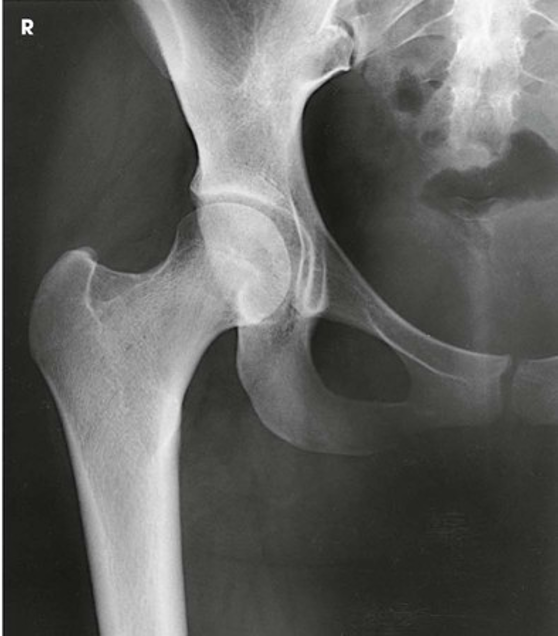

AP Projection; Hip

AP Projection; Hip (CR & SS)

The resulting image shows the head, neck, trochanters, and proximal one third of the body of the femur. In the initial examination of a hip lesion, whether traumatic or pathologic in origin, the AP projection is often obtained using an IR large enough to include the entire pelvic girdle and upper femora. Progress studies may be restricted to the affected side.

AP Projection; Hip (Eval Criteria)

• Evidence of proper collimation

• Regions of the ilium and pubic bones adjoining the pubic symphysis

• Hip joint

• Proximal one third of the femur

• Femoral head, penetrated and seen through the acetabulum

• Entire long axis of the femoral neck not foreshortened

• Greater trochanter in profile

• Lesser trochanter usually not projected beyond the medial border of the femur, or only a very small amount of the trochanter visible

• Any orthopedic appliance in its entirety

• Soft tissue and bony trabecular detail